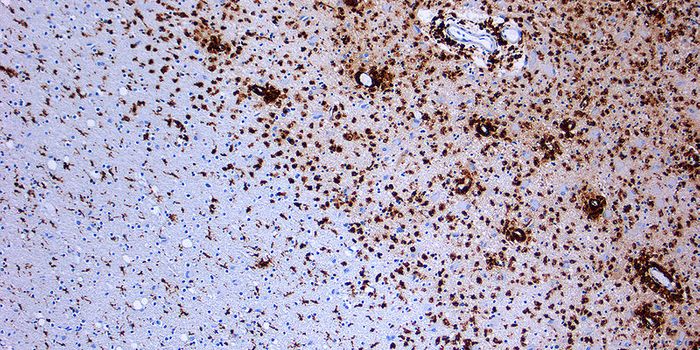

OCT 03, 2017NeuroscienceChronic traumatic encephalopathy (CTE) the brain disorder that experts agree is a result of repeated blows to the head t ...

FEB 09, 2024CancerHistopathology describes the process of examining pieces of tissue using a microscope. Light microscopic (LM) exam ...